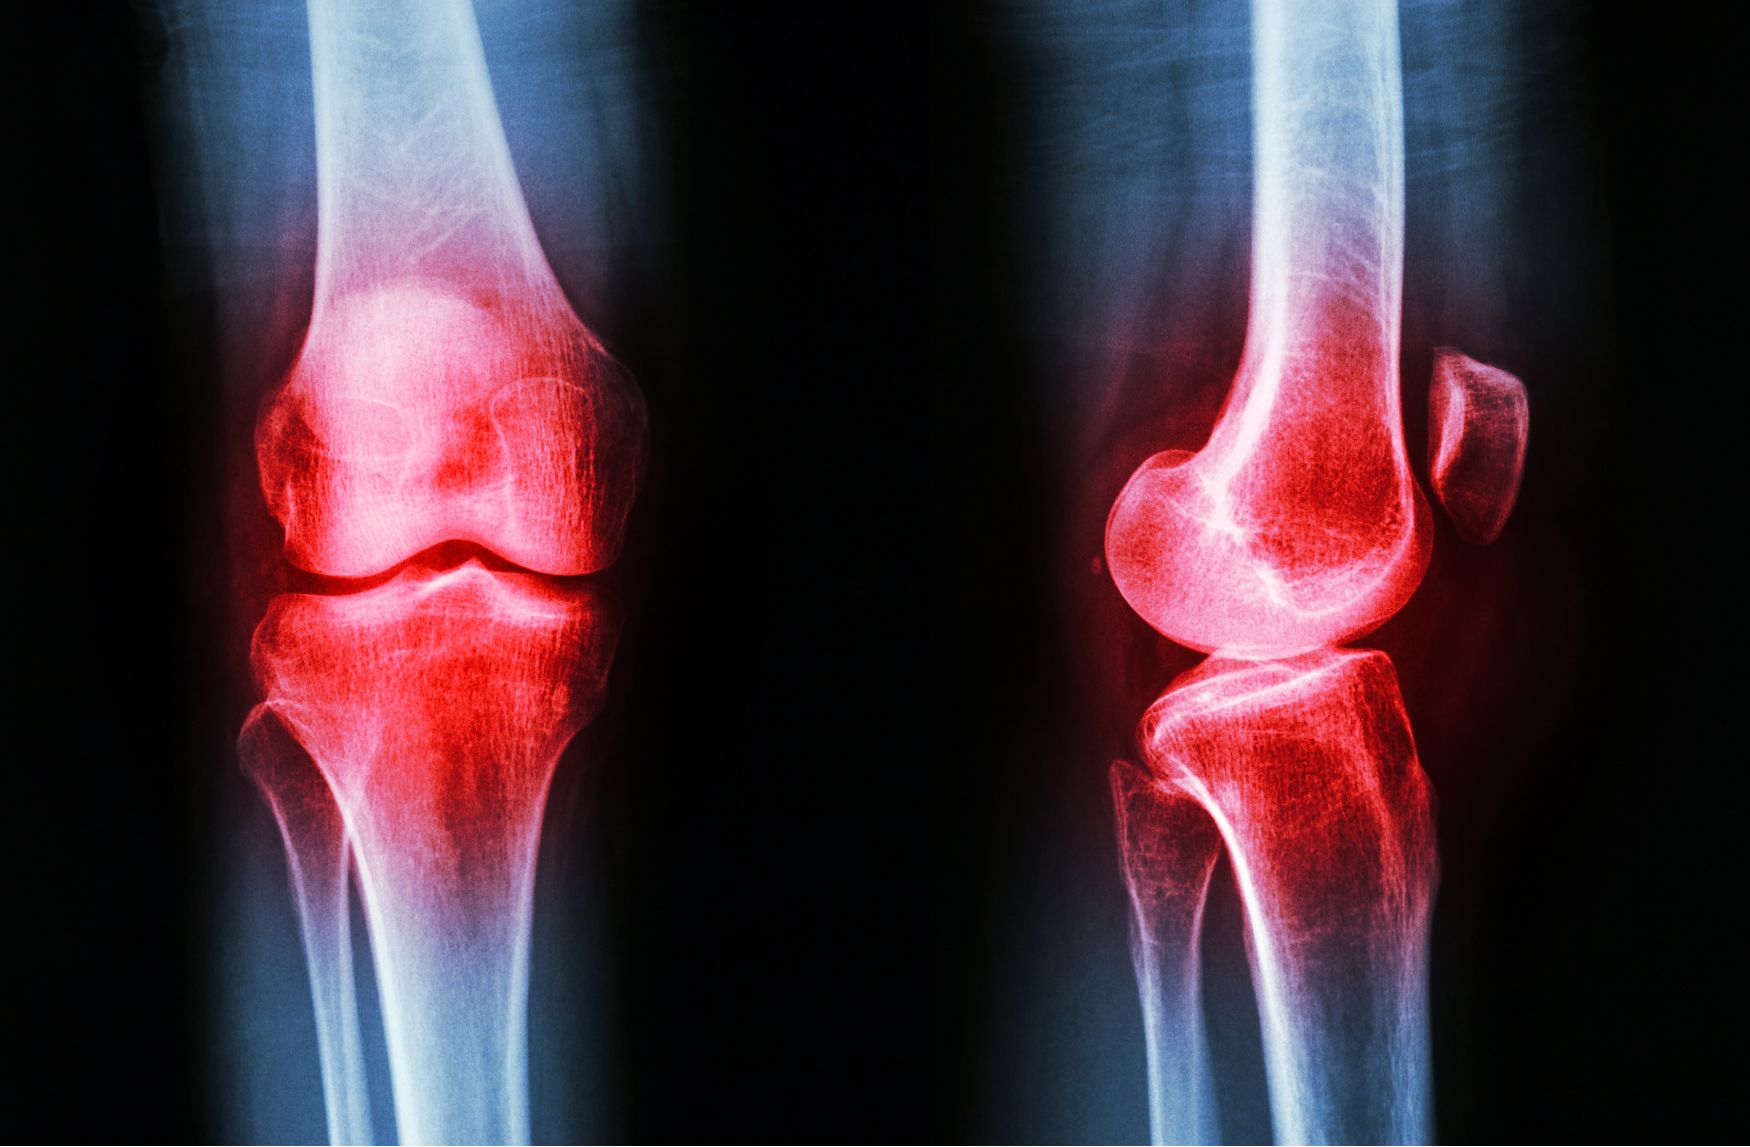

간혹 무릎 염증이 만성화되어 쉽게 가라앉지 않는 경우들이 있습니다. 이런 경우에는 병원에 내원하셔서 뼈에 이상이 없는지 X-ray 검사를 실시하는 것을 권장드리며, 병원에서는 빠르게 염증과 통증을 가라앉히기 위해 스테로이드성 약물을 처방하기도 합니다. 스테로이드는 일반 소염제에 비해서 효과가 더욱 빠른 편입니다. (잦은 사용은 좋지 않습니다)